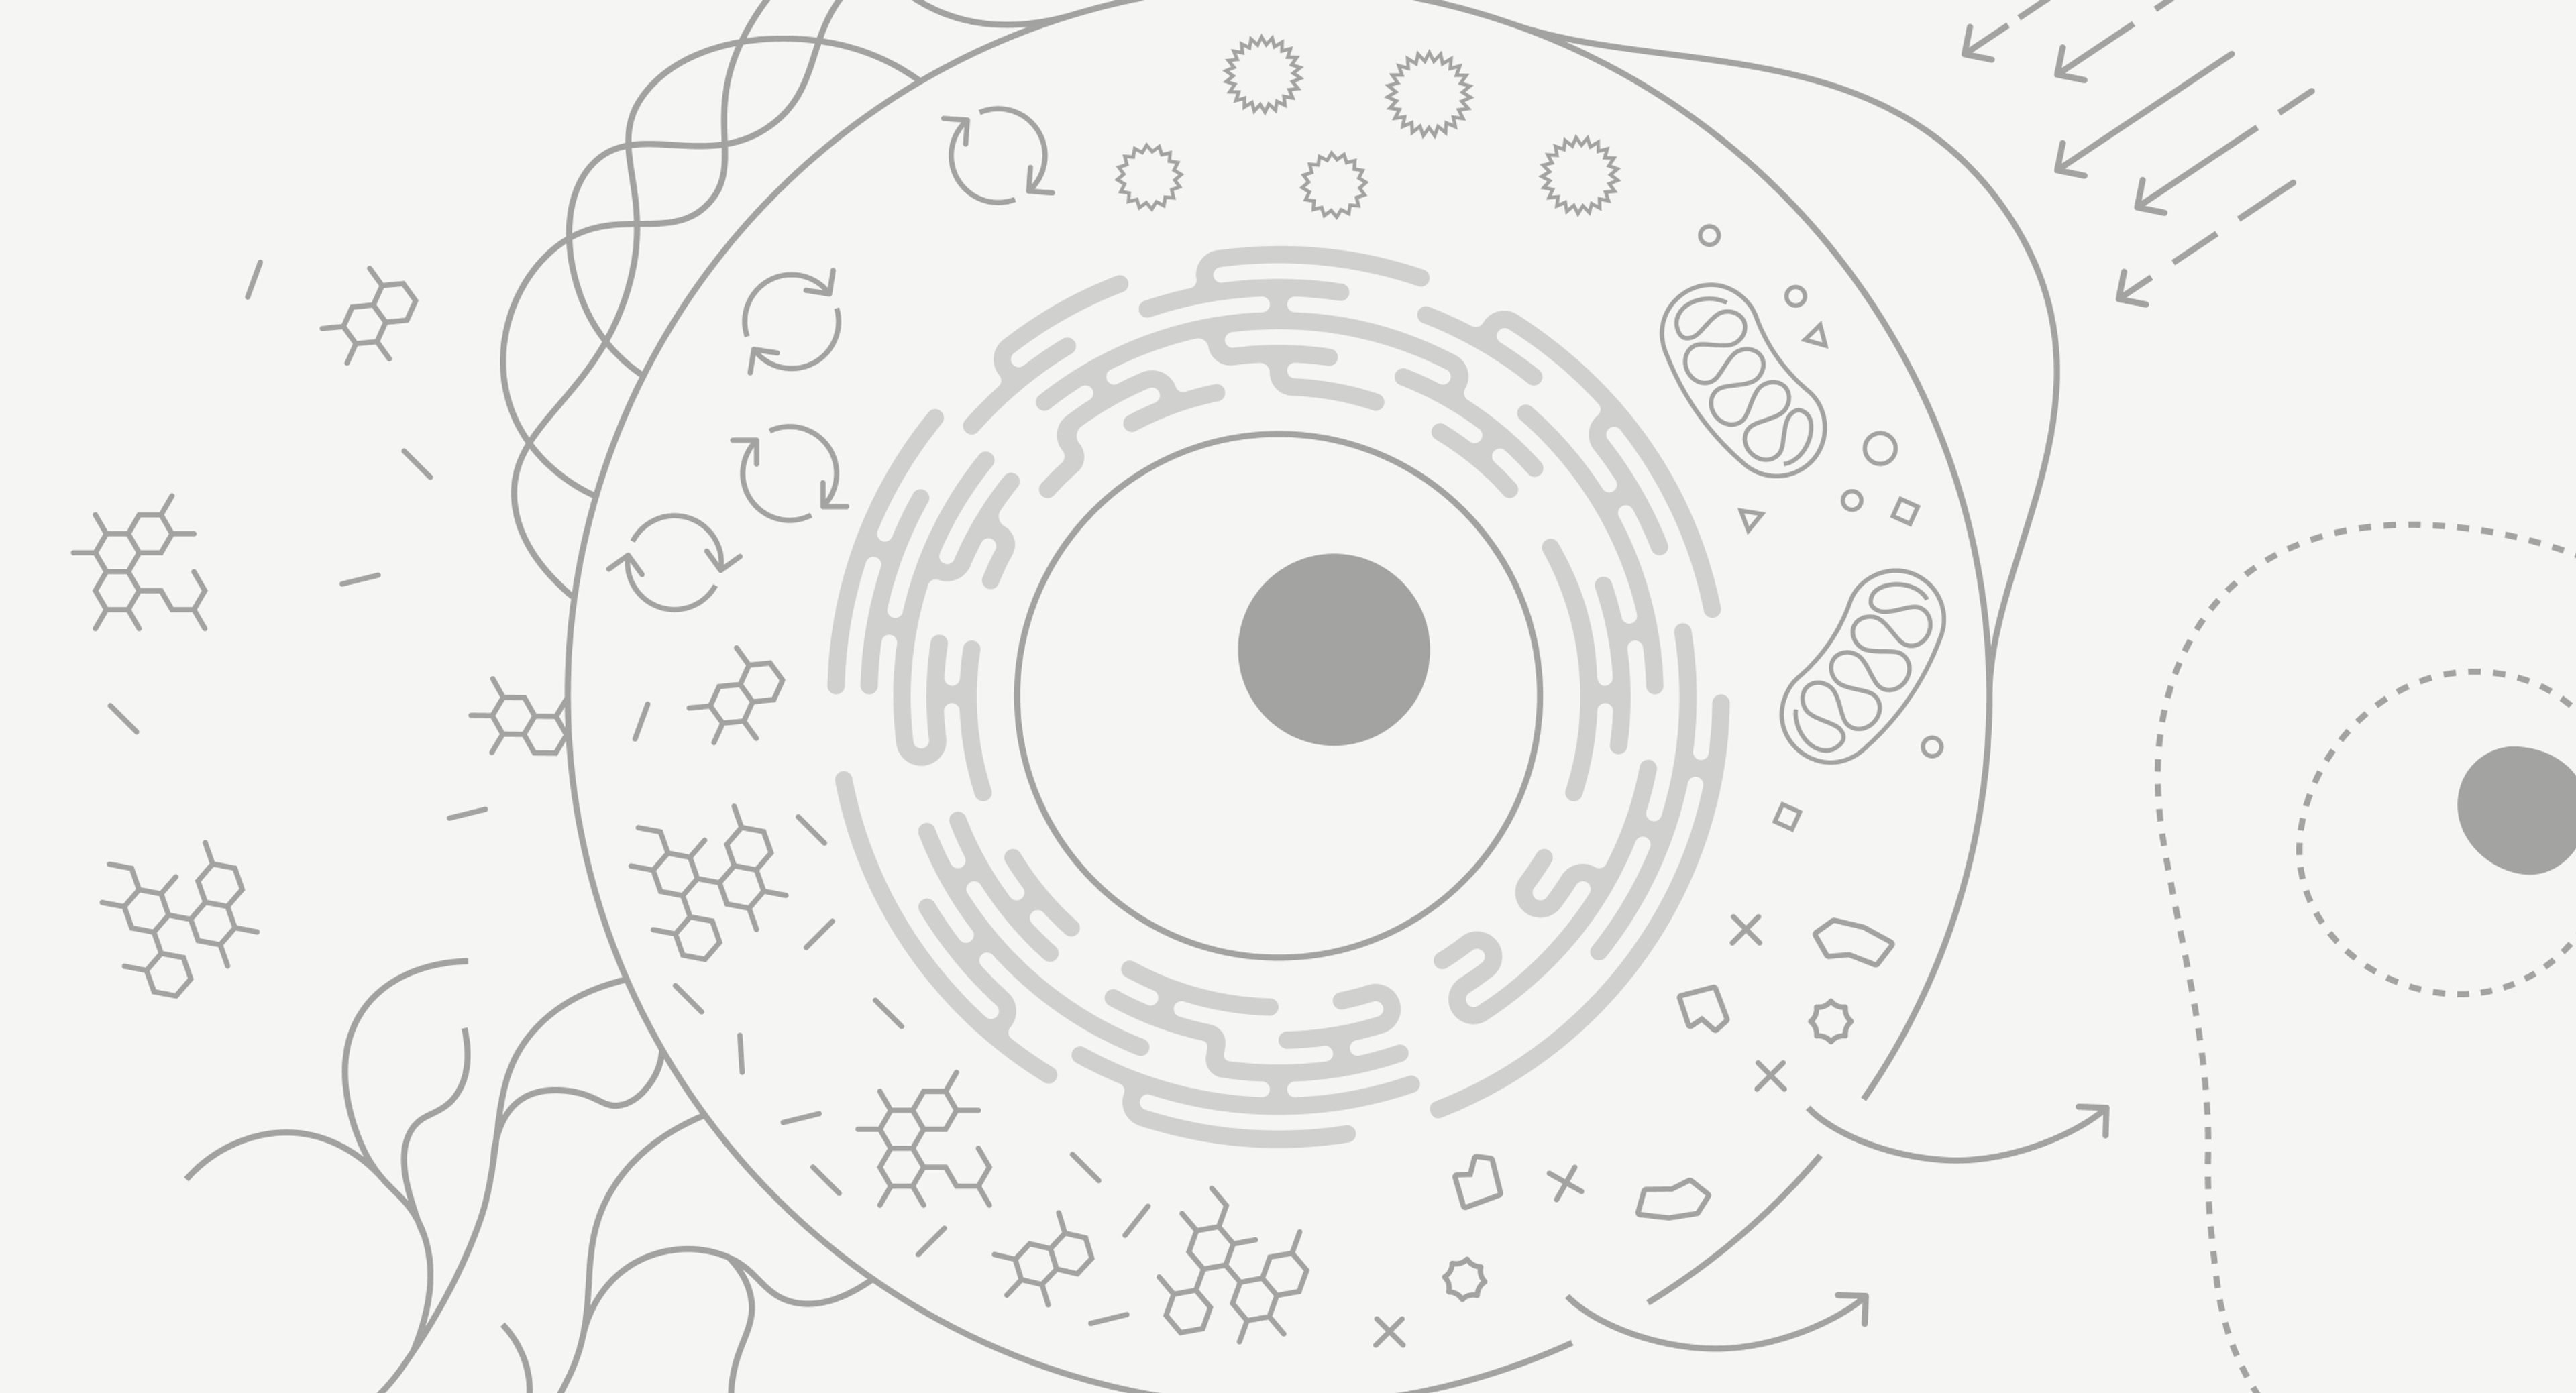

Diagramatic illustration of a human cell and it's processes.

The hallmarks of aging are complex biological processes that occur in our cells.